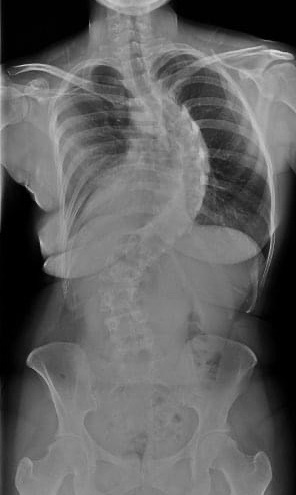

I also have scoliosis, yet no one has asked me why I want that label. I have scoliosis, it’s severe and it causes me constant pain. I can’t just pretend it isn’t there, it’s a physical disability and it’s real.